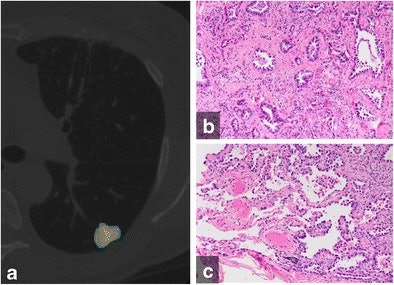

The CANARY software package was designed to identify pulmonary nodules that are aggressive and potentially cancerous from those that are not aggressive and potentially could be treated with less extensive surgery. It assesses voxel densities of pulmonary nodules on high-resolution CT scans and then categorizes risk based on voxel proportion and clustering. Voxel densities are classified as having low-, intermediate-, or high-risk components, each of which are color-coded as an overlay on the image.

The software can noninvasively stratify the risk that lung adenocarcinomas can pose by characterizing the nodule as noninvasive adenocarcinoma in situ (AIS), or invasive subtypes such as minimally invasive adenocarcinoma (MIA) or invasive adenocarcinoma (IAC). While CANARY has been shown to be accurate in assessing the histology and outcome in a morphologically diverse number of lung adenocarcinomas, it has not yet been tested in lung adenocarcinomas manifesting as pure ground-glass nodules, which have a morphologically more uniform appearance on CT.

The group used CANARY to retrospectively assess 64 biopsy-proven pure ground-glass nodules from 59 patients. Of these, 28 (44%) were AIS, 26 were MIA, and 10 (16%) were IAC. The nodules had an average diameter of 14.4 ± 5.3 mm on CT.